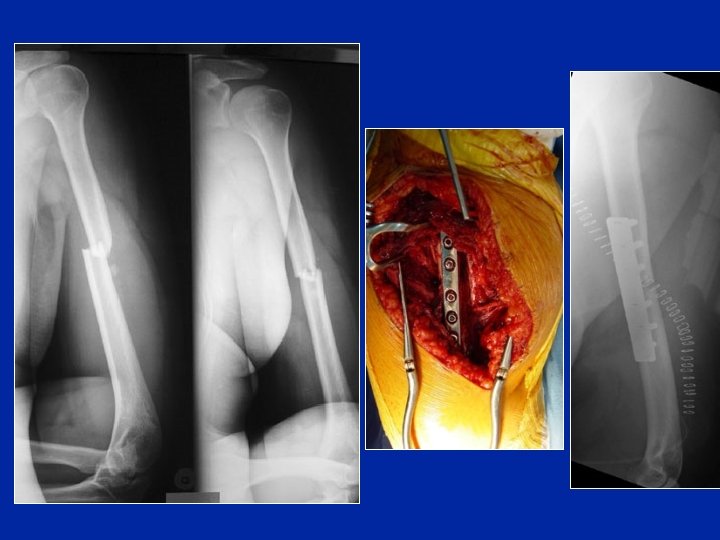

Osteosintesi con placca Inconvenienti: • Accesso chirurgico largo • Devascolarizzazione dei frammenti • Esposizione

Osteosintesi con placca Inconvenienti: • Accesso chirurgico largo • Devascolarizzazione dei frammenti • Esposizione del nervo radiale • Ritardo di consolidazione Placca posteriore Placca laterale

Osteosintesi mediante placca avvitata: Rischio di pseudartrosi ++